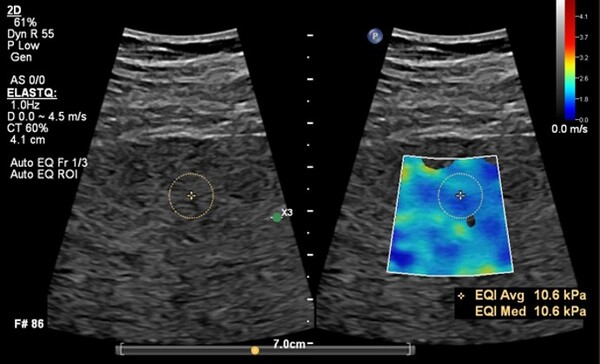

새로운 버전의 에픽 엘리트에는 워크플로우를 향상하는 간섬유화 검사 기능인 ‘오토 엘라스트큐(Auto ElastQ)’를 새롭게 탑재했다. 전단파 탄성 초음파(Shear Wave Elastography,SWE) 데이터를 자동으로 분석하고 최적의 측정 프레임과 검사 관심 영역(ROI, Region of Interest)을 설정하는 기능으로 검사 효율성과 진단 정확도를 향상한다.

기존에는 의료진이 수동으로 프레임과 ROI를 지정해야 했으나, 이제는 시스템이 자동으로 최적의 측정 위치를 설정하여 더욱 빠르고 정밀한 검사가 가능하다. 이를 통해 검사 시간이 기존 대비 60% 단축되고, 키 스트로크(조작 횟수)가 29% 감소해 의료진의 업무 부담을 줄이는 데 기여한다.